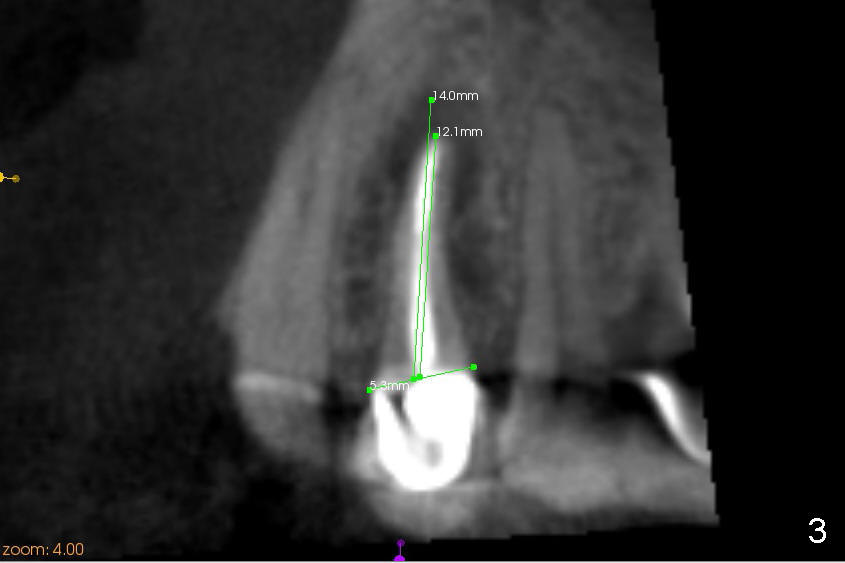

The radiolucency is more or less confined to the apical region. The fistula is most likely due to endo failure. The buccal and lingual canals fuse before exit. Debridement and filling were not done properly. Although root canal retreatment is an option, implant replacement offers long term prognosis.

It appears that there is a buccal bony defect coronally. The implant is placed more or less palatally (in position and tilt) for better restoration. Either bone level (4.5x14 mm, Fig.1) or tissue-level (4.5x20, Fig.2) implant is placed. The diameter is more or less determined by the adjacent teeth (Fig.3). A 4.5x14 mm bone level implant should obtain sufficient primary stability (Fig.4). If not, either the diameter or length of the implant is to be increased.